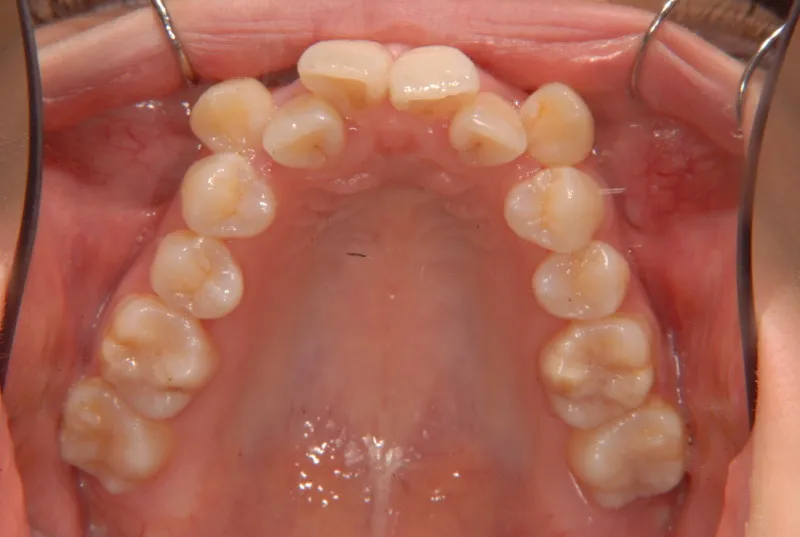

八重歯で笑うと尖った歯が目立ちます。

上下ガタガタで、下の歯は癒合歯(2本がくっついて1本の歯)です。

コルチコトミーという矯正法で歯根への負担を軽減しながら治療しました。

治療回数71回、3年5ヶ月の治療期間で矯正治療を終了しました。

主訴が改善され、ご満足頂きました。